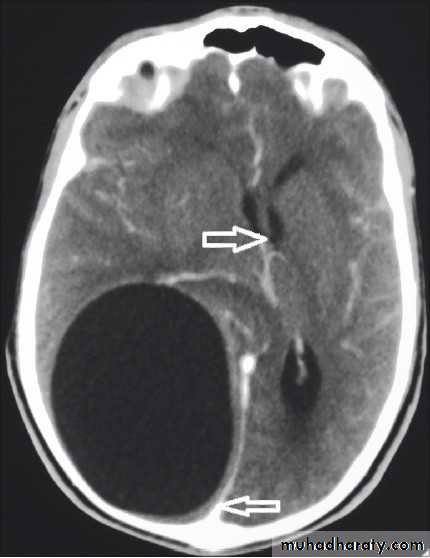

Diagnosis;

C.T. scan: very well circumscribed orange-like hypodense area with ventricular shift.* Do CXR to exclude lung involvement .